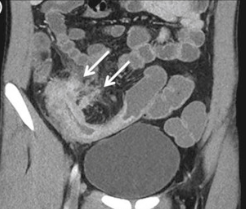

Source control

Occult subcutaneous abscess in cellulitis New abscess formation in intraabdominal infection Empyema in community-acquired pneumonia Visceral or skeletal abscess in patient with bacteremia Failure to remove a central venous catheter